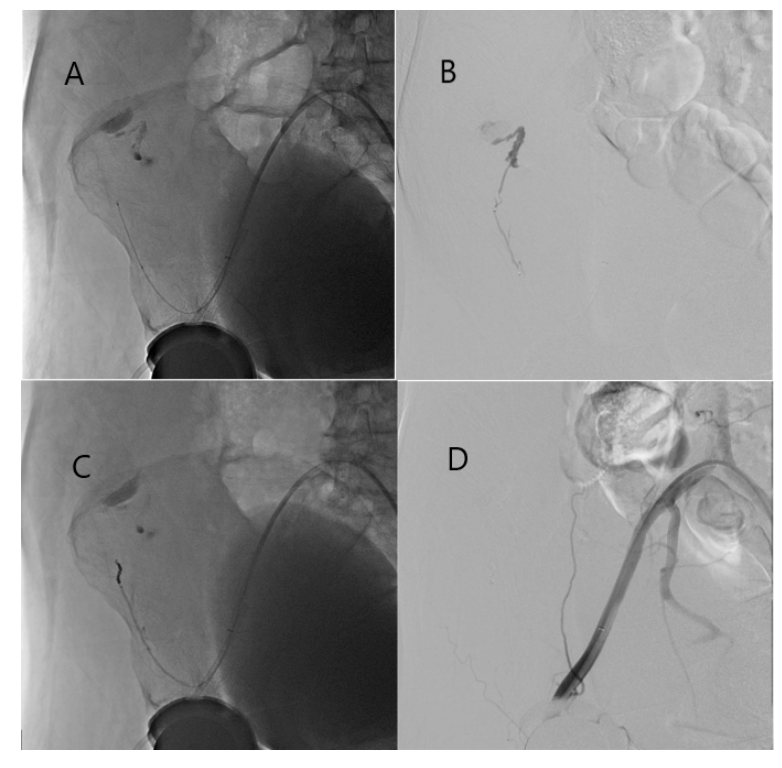

Contralateral left femoral access was obtained. An up-over sheath was advanced to the right external iliac artery. The right superficial iliac artery, a branch of the right common femoral artery, was selectively cannulated and hemostasis/tamponade of the perforated vessel was attempted using prolonged balloon inflations; however, bleeding continued. Gelfoam embolization and 2 coils were finally required for complete obliteration of the vessel and cessation of the bleeding (Figure 4).

The superficial iliac artery (SIA), the smallest of the cutaneous branches of the femoral artery, arises inferiorly to the superficial epigastric artery, at the mid-to-upper portion of the femoral head (Figure 5). It then runs in a lateral fashion, parallel with the inguinal ligament to the crest of the ilium. The distal branches of the SIA form cruciate anastomoses with branches arising from the internal iliac artery, typically from the superior and inferior gluteal arteries. The presence of these arterial anastomoses illustrates the failure of prolonged balloon inflations alone to stop the bleeding. Embolization of SIA branches complemented by arterial coiling, if warranted, should be the interventional technique of choice. Surgical intervention is reserved for embolization and coiling failures.